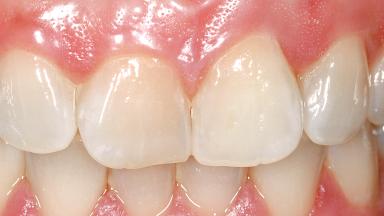

Immediate Flapless Placement of an Implant in a Maxillary Left Central Incisor Site

A 29-year-old female patient presented for treatment to replace the upper left central incisor tooth with an implant- supported restoration. The tooth had been intermittently symptomatic for the previous 12 months. The tooth had originally suffered trauma about 15 years previously. Several endodontic treatments had been performed, including an apicectomy procedure to retain the tooth. The patient was healthy and a non-smoker. She had reasonable expectations in regard to esthetic outcomes and the risk of marginal tissue recession following treatment. At medium smile, the gingival margins of the upper teeth were visible, with a display of 3 to 4 mm of the gingival margins. Gingival recession of tooth 21 and a discrepancy in the gingival levels between teeth 11 and 21 was observable during normal speech and smile.

Lip Line No exposure of papillae Exposure of papillae Full exposure of mucosa margin

Periodontal Phenotype Low-scalloped, thick Medium-scalloped, medium-thick High-scalloped, thin

Soft Tissue Contour and Volume Slightly compromised